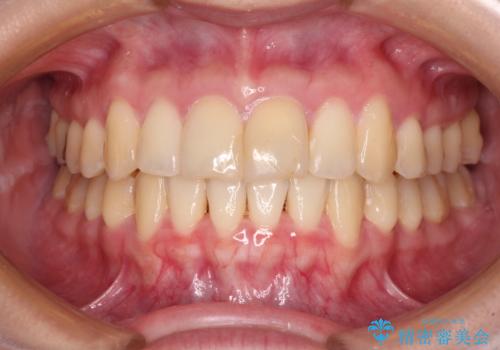

急速拡大装置 前歯の反対咬合をインビザラインで改善

- 前歯の反対咬合を気にして来院された患者様です。

上顎前歯の矮小歯は矯正治療の途中でオールセラミッククラウンを装着し、左右のバランスを整えることとしました。

急速拡大装置の使用により奥歯の咬み合わせが劇的に変わり、その変化を利用して反対咬合を改善することができました。

治療期間中は奥歯が咬み合わず、食事が取りにくいなどの不都合がありましたが、最終的にはきれいに整えることができました。